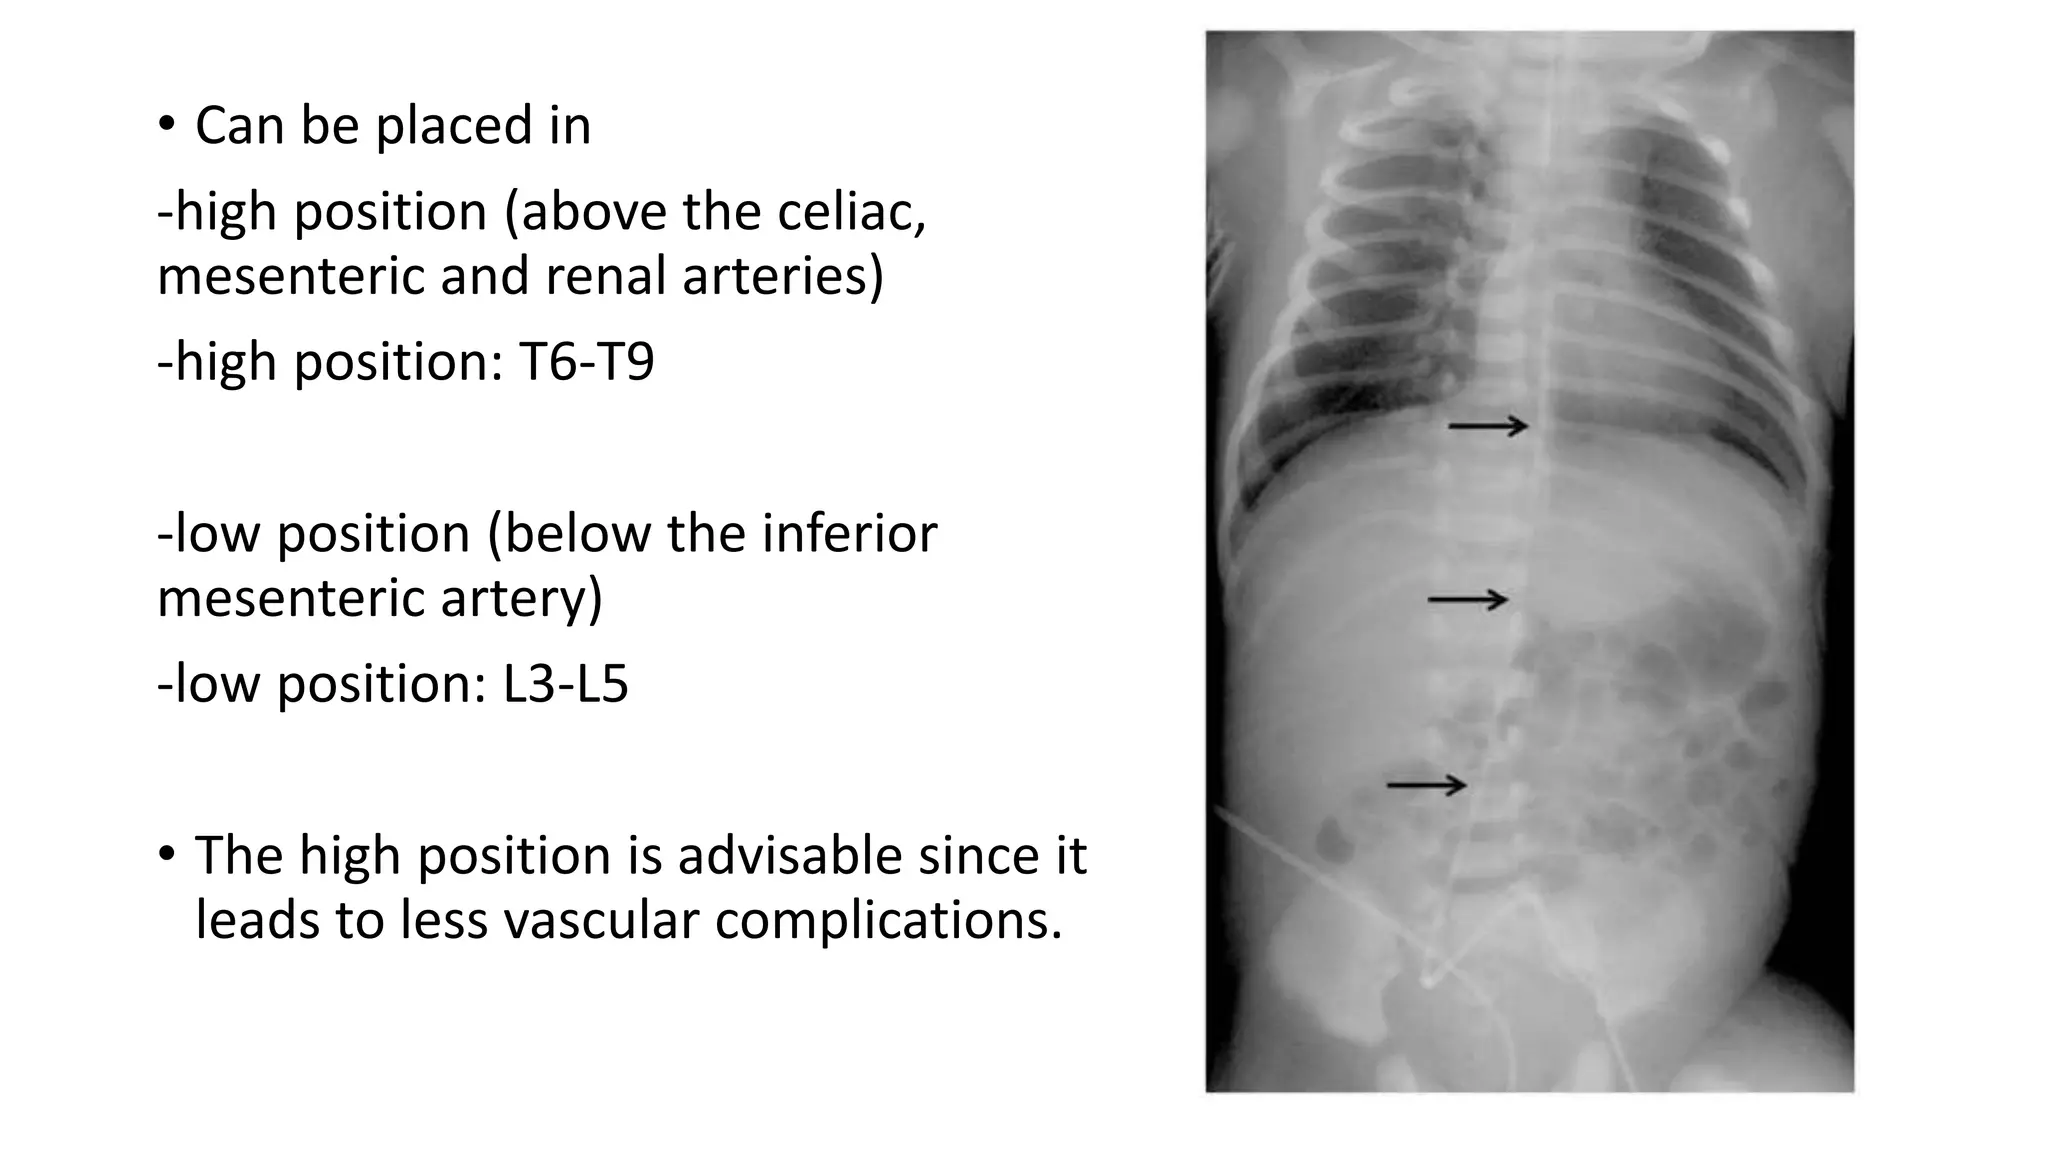

This document provides an overview of neonatal chest x-rays, including when they should and should not be performed, what a normal x-ray looks like, common positions of tubes and catheters, and common causes of respiratory distress in neonates. It discusses the appearance of a normal chest x-ray as well as conditions like respiratory distress syndrome, transient tachypnea of the newborn, meconium aspiration syndrome, and pneumonia. Surgical conditions like diaphragmatic hernia and esophageal atresia are also reviewed.